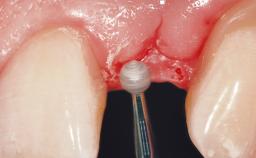

A 39-year-old male patient presented with a chief complaint of discomfort and gingival discoloration around his maxillary left central incisor. He was in good general health and was a non-smoker. His past dental history was significant because of the traumatic fracture of tooth 21 in a sporting accident at age 13. Initial dental treatment included endodontic therapy and a full-coverage restoration. The patient became symptomatic 5 years later, when structural failure of the tooth resulted in the dislodgment of the crown. Endodontic retreatment, apical surgery, and post-and-core restoration were performed.

Soft Tissue Grafting Simultaneous

Soft Tissue Contour and Volume Slightly compromised